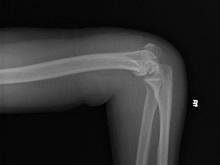

肱骨小头骨折是少见的肘部损伤。成人多发生单纯肱骨小头骨折,儿童则可发生合并有部分外髁骨折的肱骨小头骨折。该骨折易误诊为肱骨外髁或外上髁骨折。